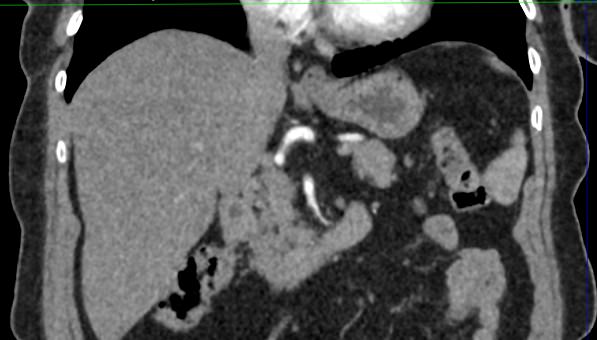

Современным высокоинформативным способом выявления патологических изменений поджелудочной железы является мультиспиральная компьютерная томография с прицельным сканированием органа. Метод КТ основан на применении рентгеновского излучения и способности органов и тканей поглощать рентгеновские лучи.

При необходимости детальной визуализации структуры железы, особенно в случае подозрения на развитие опухоли, назначается КТ поджелудочной железы с контрастом. Для этого применяются йодсодержащие контрастные препараты, которые вводятся пациенту внутривенно. Контрастное вещество, попадая в кровоток, контрастирует кровеносные сосуды и патологические очаги на фоне окружающих здоровых тканей.

Контрастирование позволяет отличить зоны воспаления, деструкции, разрастания фиброзной ткани и опухолевой трансформации от сохраненной паренхимы поджелудочной железы. КТ поджелудочной железы с контрастированием дает исчерпывающую информацию о состоянии органа и патологических процессах в нем.

При помощи специальных цифровых приложений данные, полученные при сканировании, преобразуются в трехмерные изображения органа, что дополнительно повышает точность и достоверность диагностики заболеваний поджелудочной железы.